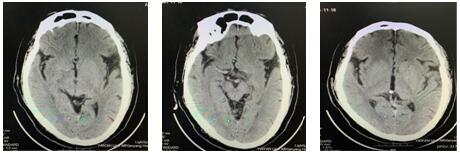

16:26急查头颅CT示:右侧额叶皮质区急性期脑梗死,结合患者症状体征考虑脑梗死急性期。请示NICU王伟伟主任,立即启动绿色通道。